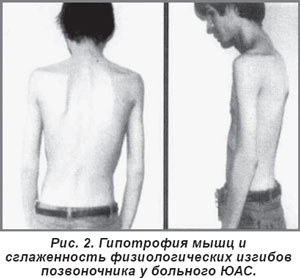

Поражение осевого скелета почти у половины больных развивается в течение первого года, а у 20-30% — уже в дебюте ЮАС. Впервые симптомы вовлечения в процесс илеосакральных сочленений и позвоночника могут выявляться в возрасте 11-14 лет независимо от возраста начала ЮАС (см. рис. 1). Первым клиническим признаком осевого поражения обычно является боль в проекции сакроилеальных сочленений, проявляющаяся как активными жалобами, так и при физикальном обследовании. Важно подчеркнуть, что используемые для клинической диагностики сакроилеита у взрослых симптомы Кушелевского практически не имеют диагностической значимости для детей, вероятно, в силу высокой пластичности тканей в детском возрасте, что препятствует созданию перерастяжения в области крестцово-подвздошных сочленений, необходимого для выявления воспаления в этой области. Большей информативностью обладает оценка жалоб пациента, а также выявление пальпаторной болезненности в проекции сакроилеальных сочленений. Симптомы сакроилеита нередко уже с момента первого появления сочетаются с поражением поясничного и нижнегрудного или шейного отделов позвоночника. Характерные для взрослых интенсивные, преимущественно ночные, боли в спине нетипичны в детском возрасте и развиваются спустя значительный промежуток времени, давая основания для формального соответствия общепризнанным диагностическим критериям (Модифицированным Нью-Йоркским критериям) АС (см. рис. 1). Чаще всего у детей можно наблюдать непостоянные жалобы на чувство усталости и напряжения в мышцах спины с воспалительным ритмом, т.е. возникающие в ранние утренние часы и уменьшающиеся после физических упражнений. Иногда выявляются локальная болезненность, ограничение объема движений, сглаженность физиологических изгибов позвоночника, особенно поясничного лордоза, региональная гипотрофия мышц (рис. 2). У части больных эти симптомы значительно уменьшаются или полностью исчезают после адекватного лечения, а повторные рецидивы могут возникнуть лишь через несколько лет.